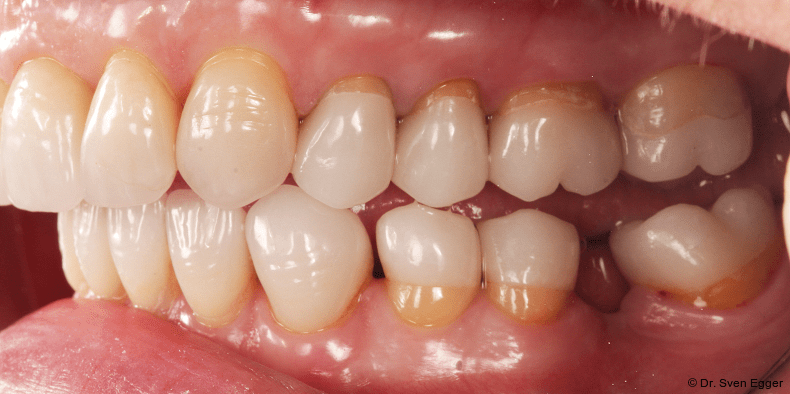

- Zahnlänge: Die Verlängerung der gesamten Oberkieferfront um ca. 1 mm empfindet die Patientin als sehr attraktiv, das entspannte Lächeln zeigt fast die gesamte Frontzahnreihe. Der Schneidekantenverlauf folgt der Konkavität der Unterlippe.

- Zahnform: Die größeren und längeren Schneide- und Eckzähne sowie die kleine Stellungskorrektur der beiden seitlichen Schneidezähne fügen sich harmonisch in das Gesamtbild der Restbezahnung ein und schenken der Patientin ein attraktives Erscheinungsbild (Abb. 15).

- Form und Größe, Charakterisierung durch den ausführenden Zahntechniker (Transparenz, Transluzenz) sowie die Oberflächenstruktur (Textur) der keramischen Veneers zeigen ein ansprechendes Erscheinungsbild. Das Längen-Breiten-Verhältnis beträgt nun circa 80 Prozent (Länge 11 mm, Breite 8 mm).

- Zahnstellung: Die leicht nach distal rotierten seitlichen Schneidezähne konnten durch die Einzelzahnrestaurationen etwas ausgeglichen werden. Durch die „Verlängerung“ der Eckzähne konnte gezielt eine gute Front-Eckzahn-Führung in die Veneerrestaurationen eingearbeitet werden.

- Zahnfarbe: Die Zahnfarbe entpricht ganz den Vorstellungen der Patientin (A2, VITA).

Zusammenfassung der ästhetischen Problematik: Es zeigt sich nun hinsichtlich der Länge (Lächeln), Form, Farbe, Stellung der Zähne sowie der rosa Ästhetik ein ansprechendes dentogingivales Erscheinungsbild. Die unteren Frontzähne haben leichten Kontakt auf den Palatinalflächen der oberen Eck- und Schneidezähne. Der Overbite beträgt 4 mm. Der Overjet 2 mm (Abb. 16+17).